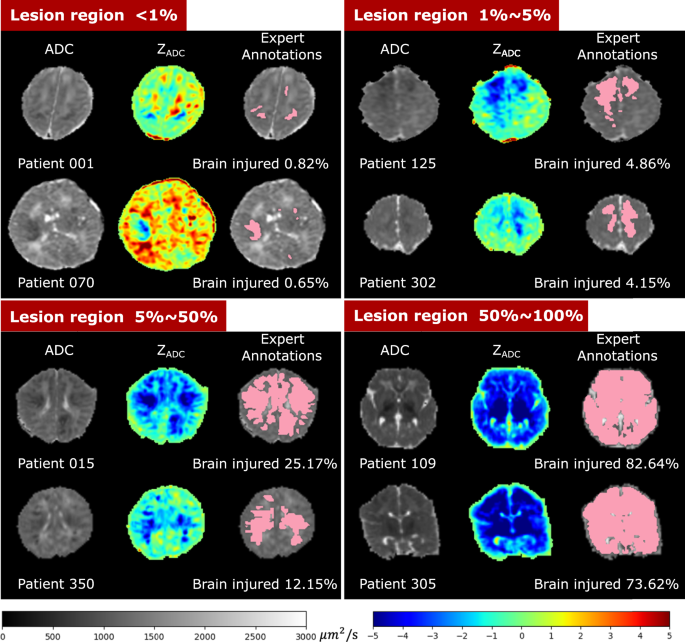

Figure 5 shows the ADC map, ZADC map, and expert annotations of example patients with different HIE lesion percentages. Two patients are shown in each of the four groups: those with lesions occupying < 1% (upper left panel), 1–5% (upper right panel), 5–50% (lower left panel), and 50–100% (lower right panel) of the whole brain volume. Overall, around 1 in 2 (55.64%) patients had HIE lesions occupying less than 1% of their brain volume, and 3 in 4 patients (75.19%) patients had lesions occupying less than 5% of their brain. This confirms that HIE lesions detectable in the diffusion MRI in our cohort are often small.

Visualization of patients with different lesion percentages. In every patient, the left image is the ADC map (skull stripped) with range of ADC values designated by the gray scale bar, the middle is the computed ZADC map with range of Z-scores designated by the rainbow scale bar, and the right image is the expert-annotated lesion regions (pink) overlaid on the ADC map. Percentages of injury were calculated by the volume of the expert-annotated lesion regions divided by algorithm-extracted whole brain volumes (including ventricles).